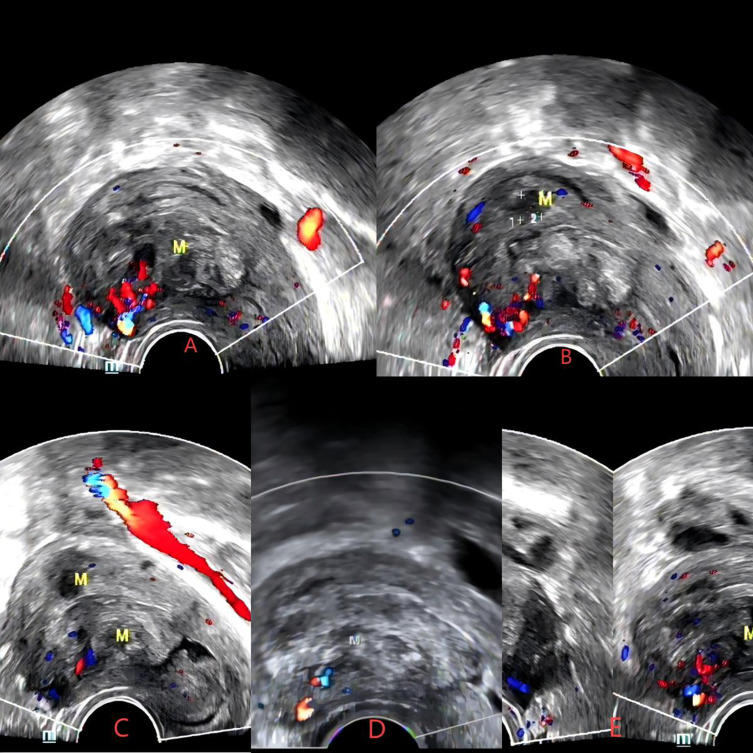

宫腔镜子宫肌瘤切除术是有生育需求的妇女切除粘膜下肌瘤的一线治疗方法。然而,面对大直径的2型粘膜下肌瘤,患者在宫腔镜检查时出现子宫穿孔、液体超载等并发症的风险更大。当2型粘膜下肌瘤直径大于4cm时,采用高强度聚焦超声(HIFU)、药物、宫腔镜三期治疗是有效且安全的。我们报告了一例30岁的未怀孕女性,她有子宫粘膜下肌瘤病史4年多,以月经量大、月经延长和继发严重贫血为主要症状。患者最初的盆腔磁共振结果提示2型子宫黏膜下肌瘤,直径大于4cm。我们首先对患者行HIFU,随后患者口服米非司酮片3个月,在宫腔镜手术前将患者的肌瘤类型转为0型,最终成功完成宫腔镜子宫肌瘤切除术(HM)。最后,我们得出结论,当2型粘膜下肌瘤直径超过4cm时,术前应考虑应用HIFU联合药物治疗,以最大限度地缩小肌瘤,改善贫血、痛经等症状,减少宫腔镜手术所需时间,提高手术安全性。

Hysteroscopic myomectomy is the first-line treatment for the removal of submucosal myoma in women facing fertility requirements. However, in the face of large diameter type 2 submucosal myoma, patients are at greater risk of complications such as uterine perforation and fluid overload during hysteroscopy. When the diameter of type 2 submucous myoma is greater than 4cm, the three-phase treatment of high intensity focused ultrasound (HIFU), drugs and hysteroscopy is effective and safe. We shared a case of a 30-year-old non-pregnant woman, who had a history of uterine submucous myoma for more than 4 years with symptoms of heavy menstruation, prolonged menstruation and secondary severe anemia. The patient's initial pelvic magnetic resonance results suggested a type 2 uterine submucous myoma with a diameter of more than 4cm. We first performed HIFU on the patient, followed by the patient's oral intake of mifepristone tablets for 3 months, and prior to hysteroscopic surgery, the patient's fibroid type was shifted to type 0, and finally successfully completed hysteroscopic myomectomy (HM). Finally, we conclude that when the diameter of type 2 submucosal myoma exceeds 4 cm, preoperative application of HIFU combined with drug treatment should be considered to maximize the reduction of fibroids, improve symptoms such as anemia and dysmenorrhea, reduce the time required for hysteroscopic surgery, and improve the safety of surgery.